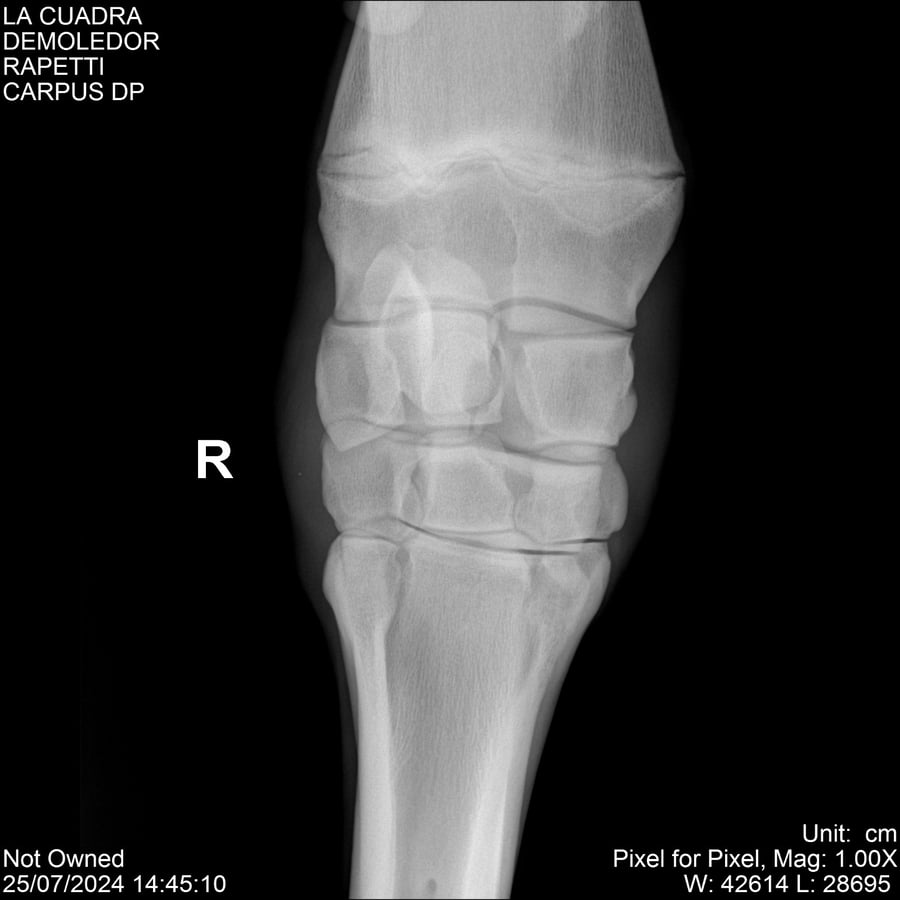

LOTE 14, DEMOLEDOR 🔥 🔥 🔥 Lote Anterior Volver al remate Lote Siguiente Ficha Contacto Montevideo - Ficha del Lote Identificador: #284454 Categoría: Yeguarizos Montevideo - 89 Visualizaciones ClicData Contacto Empresa: Abelenda N. R., Walter Hugo Nombre*: Teléfono* : E-mail* : Mensaje Enviar Registrese gratis Este contenido Exclusivo está disponible sólo para usuarios registrados Ingresar